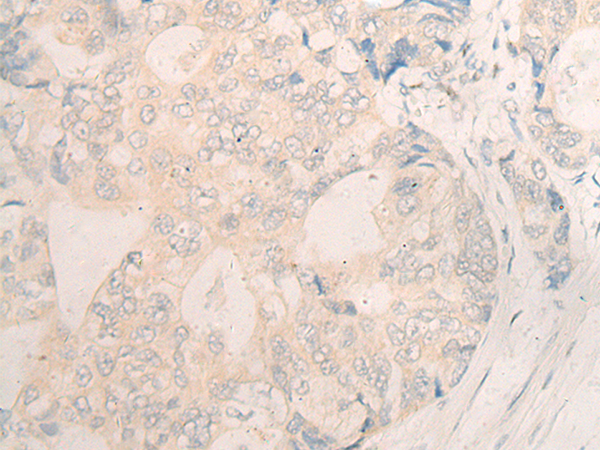

分类: 科研抗体货号: P06359别名: C2orf37应用: IHC反应种属: Human, Mouse, Rat